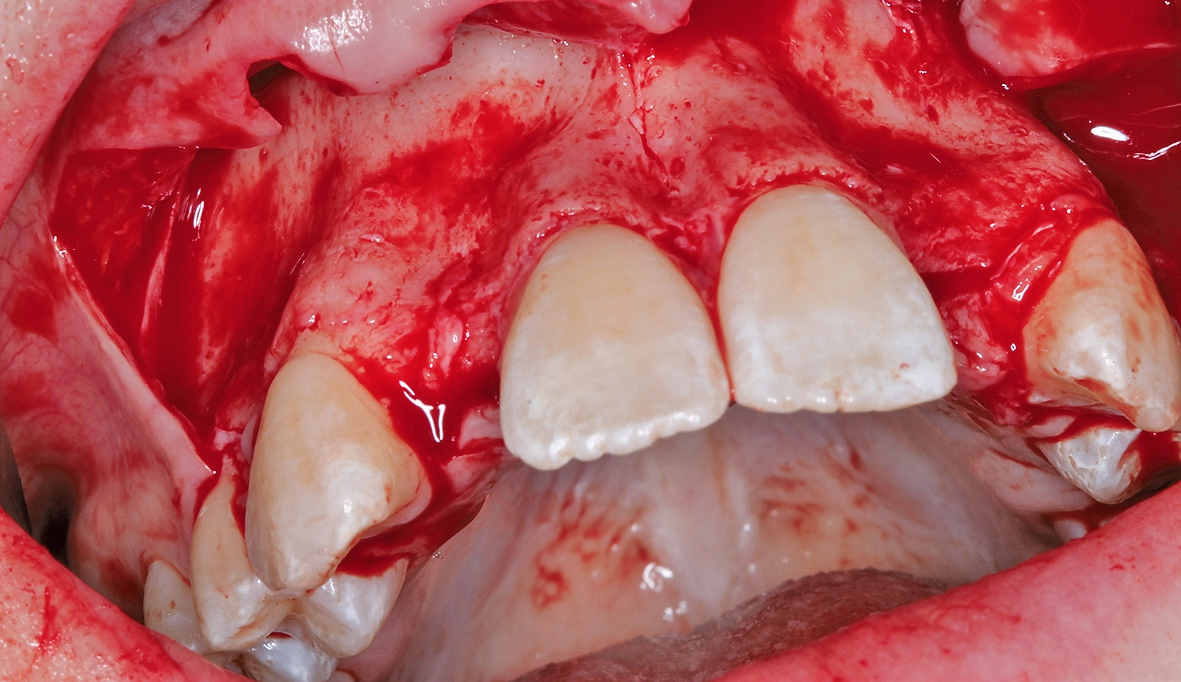

Eine 17-jährige Patientin wurde an unsere Praxis mit dem Wunsch nach einer festsitzenden implantatprothetischen Versorgung der lateralen Schneidezähne 12 und 22 überwiesen. Nach entsprechender Aufklärung und intensiver Beratung wurde zunächst ein DVT erstellt, um das genaue Ausmaß der dreidimensionalen Knochenresorption in regio der fehlenden lateralen Schneidezähne regio 12 und 22 beurteilen zu können. Die röntgenlogische Auswertung ergab eine hochgradige horizontale Alveolarfortsatzbreite von knapp 3 mm in regio 12 respektive von knapp 2,5 mm in regio 22 mit stark ausgeprägter konkaver Kontur der bukkalen Lamelle (Abb. 1). Allein das klinische Bild (Abb. 2 und 3) zeigte eine ausgeprägte horizontale Alveolarfortsatzatrophie in regio 12 und 22 mit ausgeprägten Konkavitäten in der bukkalen Lamelle.

Letztendlich bestand aus kieferorthopädischer Sicht keine Kontraindikation für eine unverzügliche chirurgische Intervention mit nachfolgender implantatprothetischer Versorgung bei derart fortgeschrittener horizontaler Atrophie in regio 12 und 22 (2,5 mm mit großer Konkavität). Insofern wurde nach erneuter intensiver dokumentierter Beratung und Aufklärung wie auch wirtschaftlicher Aufklärung nach entsprechender beidseitiger Leitungsanästhesie am Foramen infraorbitale und zusätzliche intraoralen und vestibulären Infiltrationsanästhesien zunächst ein breiter Mukoperiostlappen von regio 14 bis 24 gebildet (Abb. 4) und zur Förderung der Durchblutung des allogenen Transplantates wurden entsprechende Bleeding-Points (entsprechende Perforation der bukkalen Kortikalis) gesetzt (Abb. 5). Die mit Hilfe von CAD/CAM durch das Labor ProDent (Zahntechnikermeister Thomas Blaschke) hergestellten kortikospongiösen Blöcke nach DVT-Auswertung wurden mit entsprechenden Osteosyntheseschrauben fixiert (Abb. 6) und mögliche Restspalträume mit allogener Spongiosa abgedichtet und lateral auskonturiert.